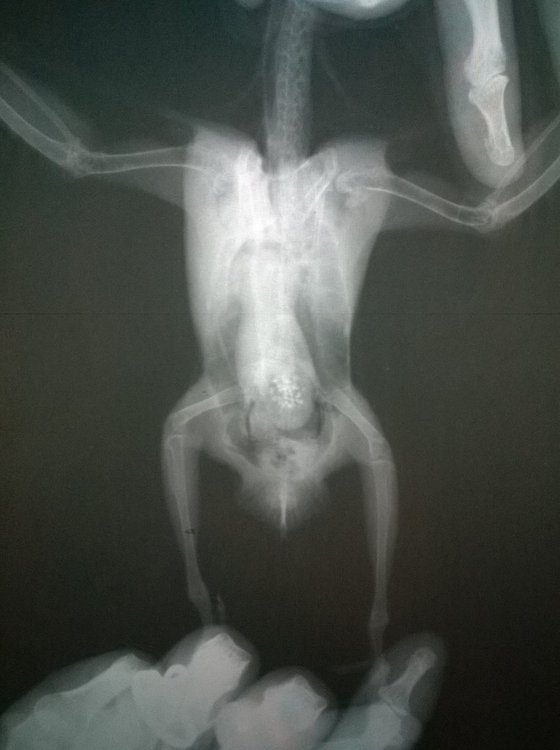

Неразлучник перестал летать, когда посмотрела, обнаружила на внутренней стороне крыла шишечку, сделали рентген, фото прикладываю. Не летает, крыло отпустилось и дрожит, продолжается больше месяца, обратиться больше не к кому, у нас нет специалистов в городе. Помет у попугая не менялся, активность хорошая, кушает тоже хорошо -

Добрый день! Обращаемся к вам с просьбой большой! @OFA, @Zosia, Пожалуйста, если вы разбираетесь в ренгене, посмотрите снимки голубки. Помогите понять в чём причина осложнений у птички. Очень просим вас!